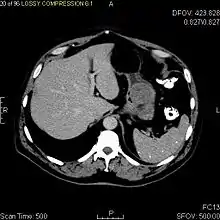

CT image of a GIST in the gastric cardia. The lesion appears submucosal, is hypervascular and protrudes intraluminally. Upper GI bleeding led to endoscopy, finding an ulcerated mass.

Non-enhanced CT image of a small GIST in the posterior stomach wall (arrow). The lesion appears subserosal. Incidental finding.